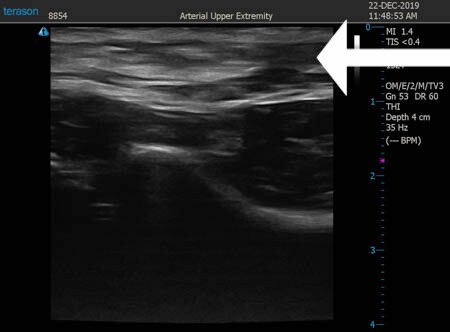

いつものように3Dタッチビュー(超音波)で

皮下脂肪層を評価してみましょう。

左肩甲骨横

上の画像の部分の皮下脂肪層をつまんでみましょう。

同様に右肩甲骨横 ↓ ↓ ↓

左ブラジャー上下

右ブラジャー上下